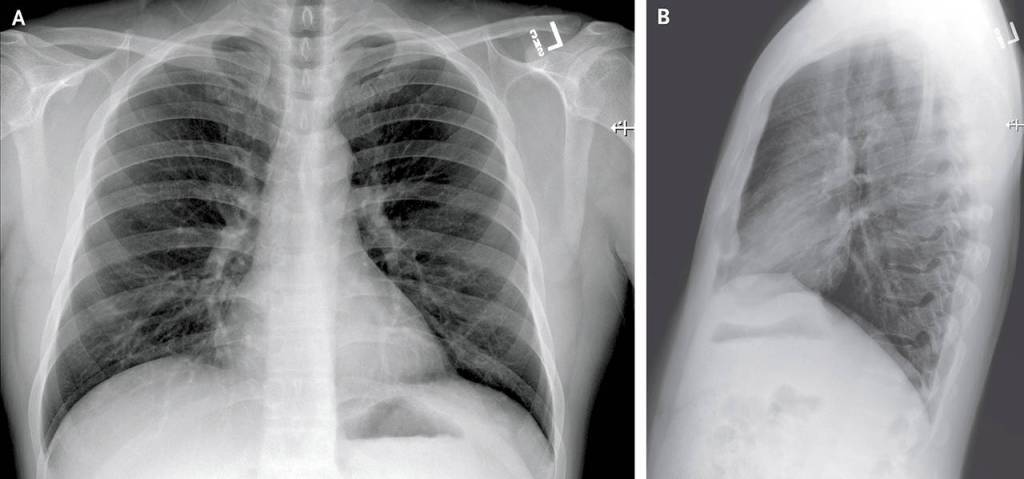

The article details the patient’s symptoms — everything from fatigue, nausea, diarrhea to a runny nose — over time and graphs his lab results. It shows X-rays of his lungs.